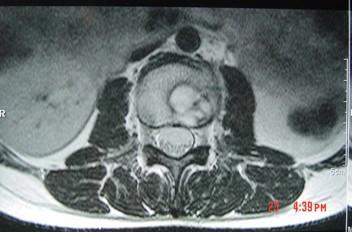

问题 男,33岁,有午后发热,夜间盗汗等,腰部疼痛,活动时加重,休息后减轻,请结合所提供图像,选择最佳答案 ( )

选项 A、骨巨细胞瘤 B、骨髓瘤 C、腰椎骨转移 D、腰椎退行性变 E、腰椎结核

答案 E